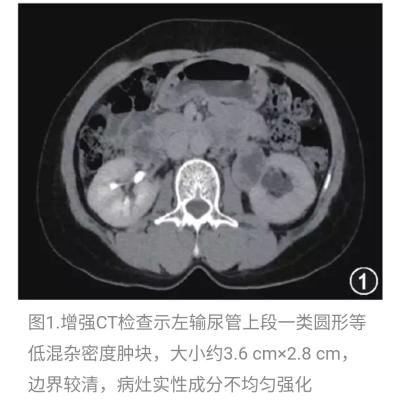

我: 入院检查情况: 肝肾功能:ALB 29g/L,余无异常,CA系列未见明显异常; 血常规:(5-14)WBC 10.64×109/L、N% 71.3%、RBC 3.84×1012/L、HGB 113g/L、 PLT 393×109/L; 尿常规:KET 微量,PRO(-);复查后KET(-),PRO 0.3g/L; 便常规:(5-13)褐色稀水便,WBC 3-5/H,RBC 0-2/H,OB(-);(5-14)褐稀糊便,WBC 大量,RBC 1-3/H,OB(+); 大便难辨梭状芽孢杆菌A毒素测定:阳性 血脂:HDL-C 0.92mmol/L↓,TC、TG、LDL-C正常; 铁四项:SI:49ug/dl,TS:21% 腹部B超:胆囊息肉,余无明显异常; 心电图正常; UCG:左室松弛功能减低,EF 61%; 胸片:主动脉弓钙化; 盆腔CT:直肠周围脂肪密度增高,纤维条索影,直肠左后方局部气体影子,胆囊结石可能,脾脏饱满。 入院诊断:直肠腺瘤切除术后              伪膜性肠炎